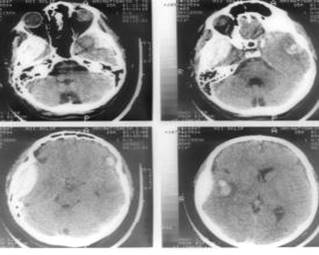

Наиболее информативным методом диагностики черепно-мозговой травмы является компьютерная рентгеновская томография, дающая представление о нарушениях анатомо-топографических соотношений в полости черепа. По изменению плотности тканей удается установить расположение, характер и степень ушибов мозга, выявить оболочечные и внутримозговые гематомы и гигромы, субарахноидальные и внутрижелудочковые кровоизлияния, отек мозга, а также расширение или сдавление желудочковой системы и цистерн основания мозга.

Окончательный диагноз ставят по результатам рентгенографии черепа в прямой и боковой проекциях (наличие повреждения костей), КТ и МРТ.